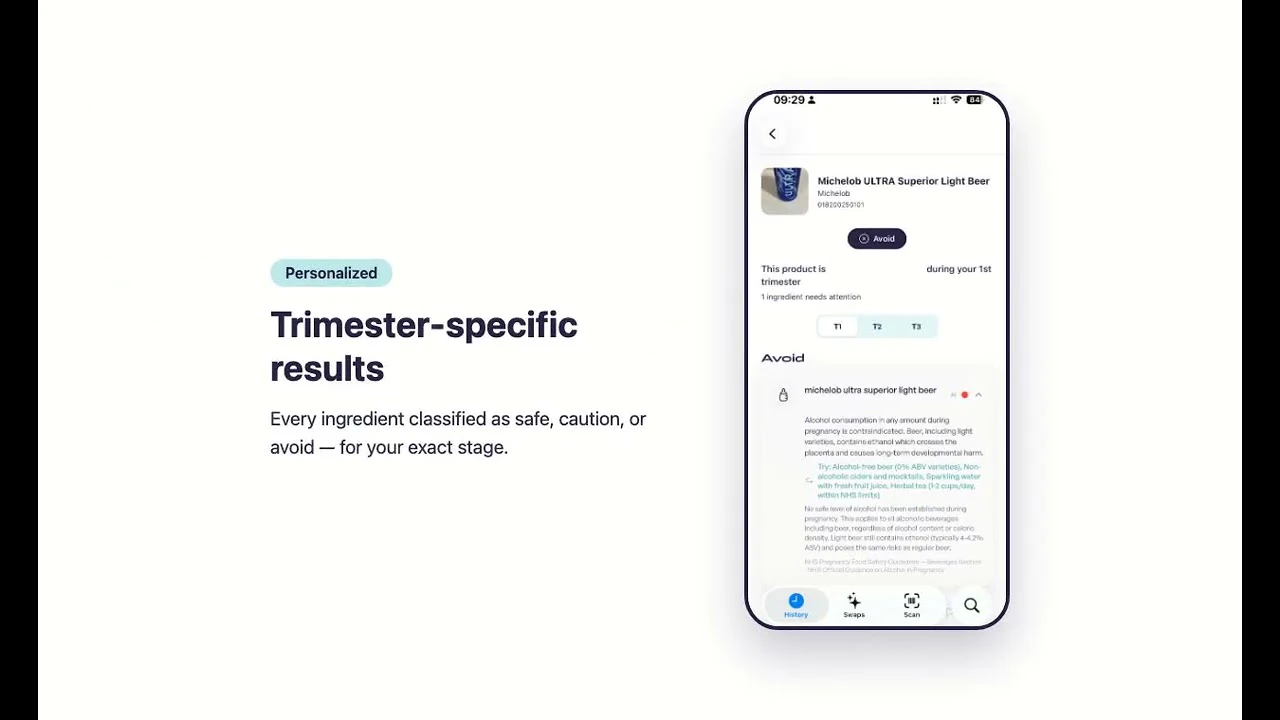

Scan any product to know it's safe during pregnancy

Oli is a pregnancy safety scanner. Scan a barcode, search by name, or photograph an ingredient la...